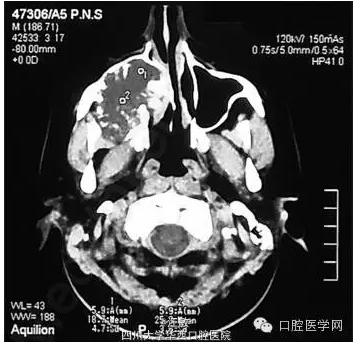

檢查發(fā)現(xiàn)患者面部不對稱,右顴骨區(qū)腫脹??趦?nèi)檢查發(fā)現(xiàn)右上頜第一磨牙至第三磨牙處牙齦腫脹,表面光滑,色暗紅。CT顯示病損已波及鼻腔外側(cè)壁和鼻中隔。

CT